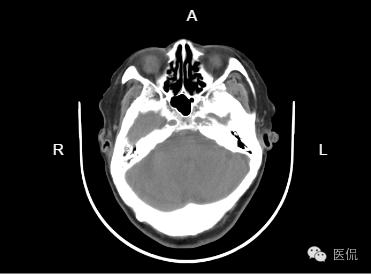

患者主诉:两年前CT显示,梗塞,现正常体检

左侧基底节区及左脑干区见小斑片状低密度灶,部分边界欠清;侧脑室旁脑白质对称性减低,余双侧大脑组织内未见异常密度,脑干及小脑形态、大小正常,内未见异,中线居中,各脑室及脑池增大、脑皮层沟回加深加宽,余未见异常。骨窗下诸颅骨无明显异常。

1、左侧基底节区及左脑干腔隙性脑梗塞。建议结合临床随访复查!

2、脑白质疏松;

3、老年性脑萎缩。